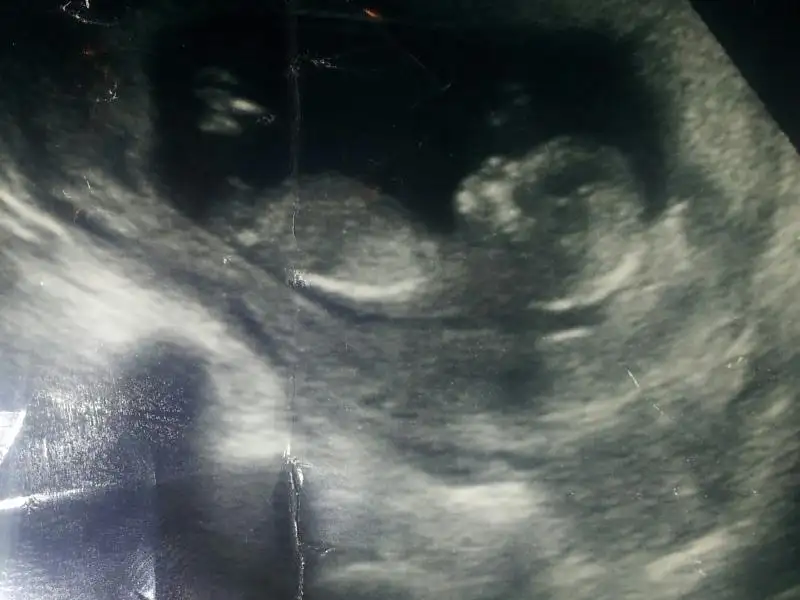

selam kızlar bu benim miniğimin geçen haftaki fotoğrafı henüz 9+5 günlük burda çok küçük ama bi bakın bakalım tahmin yürütebilecek misiniz

Merak ediyorum 9 haftalık bebekte belli olur mu?